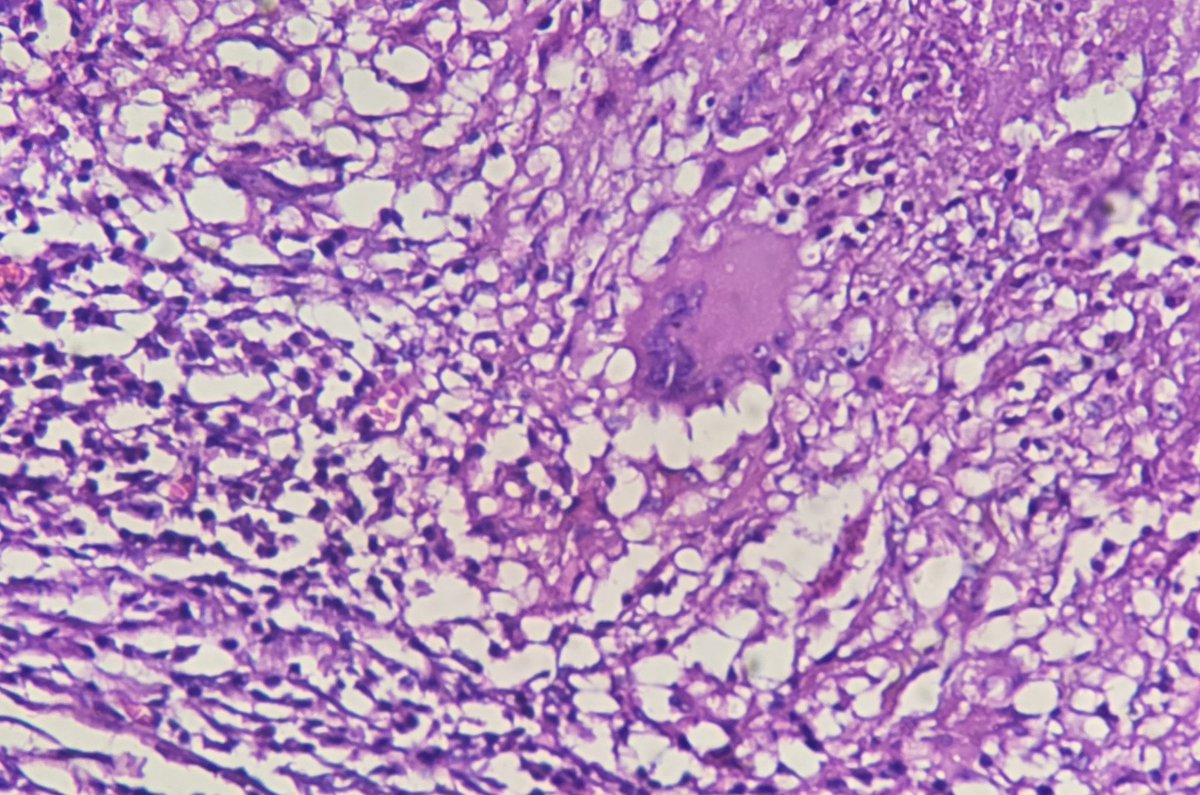

Regional lymph node metastasis of mucinous carcinoma, rectum with stage IIIC disease.

#pathology #GIPath #mucinous_carcinoma